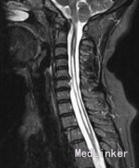

肩外展试验呈阳性,上臂缺血试验呈阳性,压颈试验阴性,臂丛神经牵拉试验阳性(以左侧为重),腱反射减弱,Hoffman征阳性,双下肢肌力、感觉基本正常;肌电图检查显示双侧正中神经、尺神经损伤电生理表现,有臂丛下干损伤可能;颈椎MRI检查显示小脑扁桃体下疝,C4-T5节段脊髓空洞症,C5-7椎间盘突出。